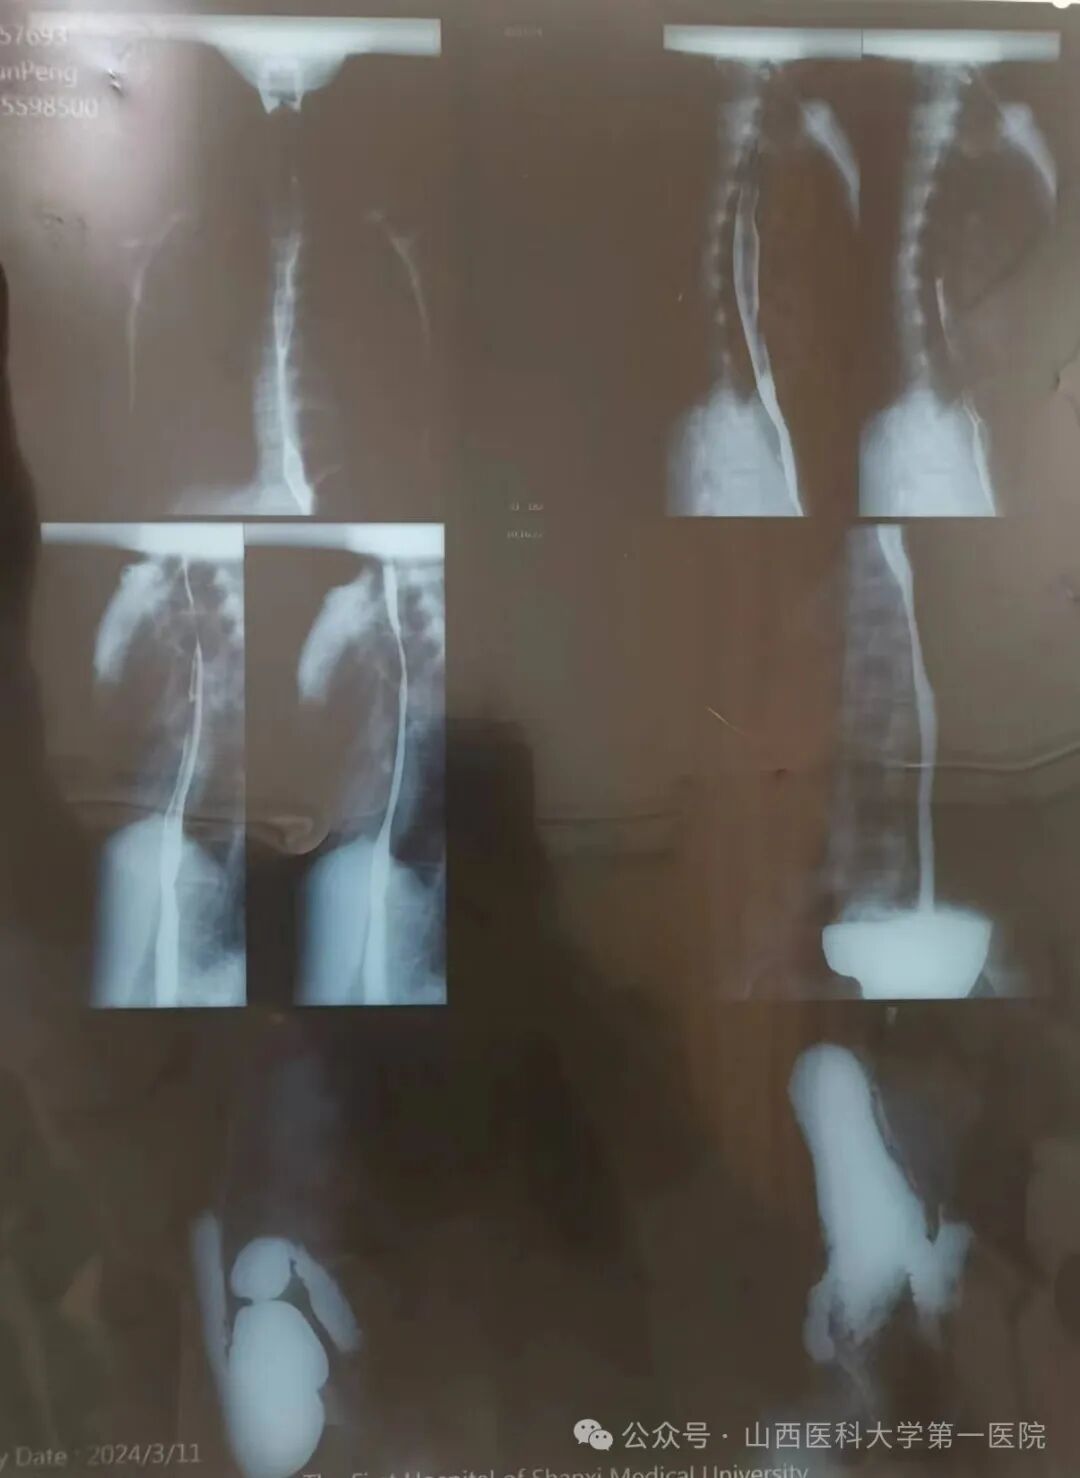

近日,山西医科大学第一医院临床营养科接诊一名重度营养不良年轻患者,该患者近两年来无明显诱因反复出现进食后腹胀、腹痛、恶心、纳差,症状进行性加重,进食量逐日减少,检查提示胃下垂及十二指肠淤滞,其带来的进食障碍使体重严重不足,BMI仅12.6kg/m2,肌肉量减少,脂肪流失,合并贫血及闭经,身体的不适导致无法正常生活学习。

十二指肠淤滞是由于各种原因引起的十二指肠阻塞,以致十二指肠阻塞部位的近端扩张、食糜壅积而产生的临床综合征,常表现为间歇性进食后腹胀、腹痛、嗳气、恶心、呕吐等。多发生于瘦长体型的中、青年女性,常见病因包括:肠系膜上动脉过长、过短;肠系膜上动脉变异,从腹主动脉分出的部位过低或分出时角度狭窄;异常粗大的静脉横压在十二指肠前方;脊柱前凸畸形使十二指肠占有的空隙减少;瘦长型或内脏下垂者肠管重量牵引肠系膜根部。患者食物摄入不足、体重下降会导致中、重度营养不良的发生,治疗原则需进食无渣食物、少量多餐,餐后采取俯卧位或左侧卧位;如患者进食量加口服肠内营养制剂达不到目标能量的60%,需要置入鼻空肠管,持续滴入营养液,改善营养状况,同时给予消化酶、胃肠动力药等;长期保守治疗无效,影响营养状况或正常工作时,可行手术治疗。